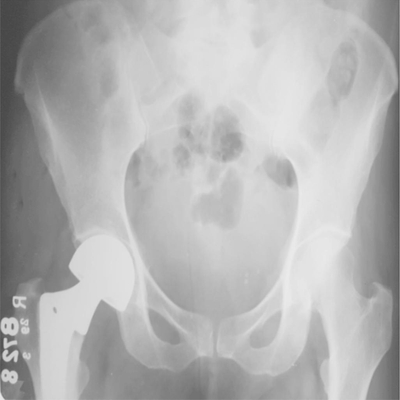

Click on an image below to view more info.